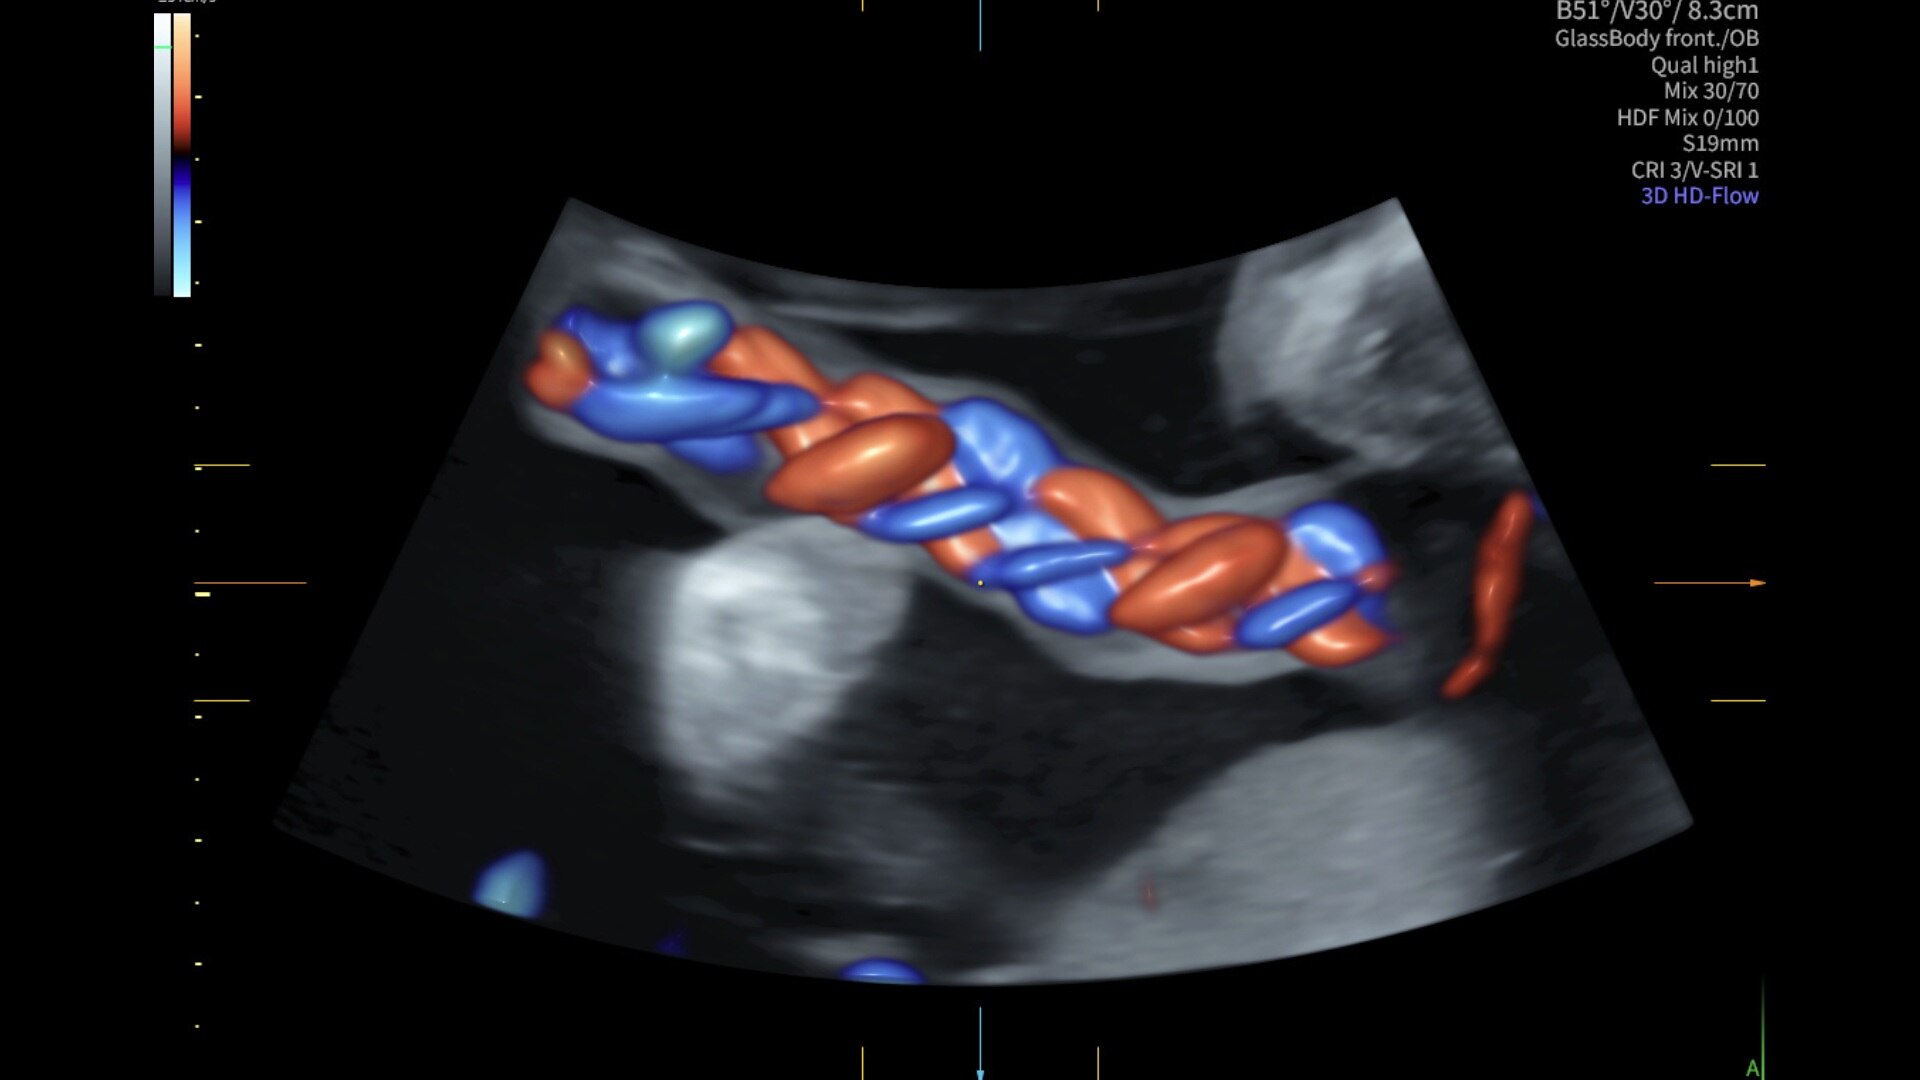

Le immagini incluse in questo documento sono esempi rappresentativi e possono variare in base alle configurazioni.